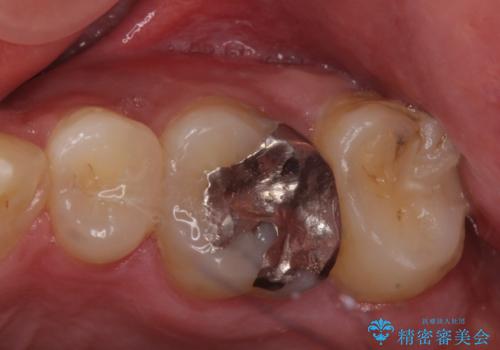

奥歯のザラザラが気になる

- 奥歯のザラザラが気になり、白い被せ物をしたいとのことで来院。

レントゲンや拡大鏡で確認をしたところ歯の表面は粗造になっていたが

う蝕があるわけではないので以下の提案を行った。

歯の表面が粗造なのは虫歯ではないが

歯の表面が溶けはじめて、虫歯になりやすい状態になっています。